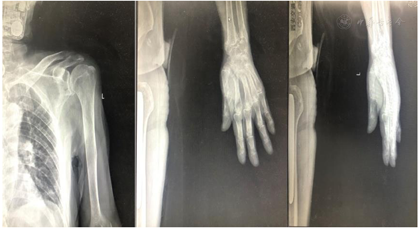

家属诉4个月余前行走时不慎被汽车撞倒在地,出现左侧髋部疼痛、活动受限,当时未有意识丧失,就诊于汉中市中心医院行X线检查示"左尺骨桡骨远端骨折,左股骨颈骨折",给予对症支持治疗,住院期间出现咳嗽、咳痰,吞咽困难,胸片"两肺中下野炎症可能,双侧少量胸腔积液",给予鼻饲饮食、气管切开、抗感染治疗,期间曾使用呼吸机。3个月前转至西安交大一附院骨科行"左侧股骨头置换术",术后一直于该院康复科行康复治疗。遗留左下肢活动受限,不能独自维持坐位、不能站立行走,左腕部活动疼痛,气管切开状态,仍有咳嗽、咳痰,体温正常,患者为行进一步康复治疗收住我科。患者自发病以来,神志清,精神欠佳,鼻饲饮食,夜修尚可,小便如常,大便肠造瘘状态,性质、量正常。

患者医学影像学检查如图1,图2,图3,图4,图5,图6,图7,图8所示,实验室检查结果如图9,图10,图11所示。

初步诊断:(1)左侧股骨颈骨折;(2)左髋关节置换术后;(3)肺部感染,气管造口状态;(4)左侧尺骨骨折;(5)左侧桡骨骨折;(6)肠造瘘术后;(7)轻度贫血;(8)低蛋白血症。

患者外伤后左侧股骨颈骨折,结合外伤史及临床影像学资料左侧股骨颈骨折诊断明确,患者高龄,骨折后卧床,因外院住院期间未行康复早期介入,患者出现肺部感染,行气管切开术,气管插管状态,身体衰弱,且患者高龄头颅CT示:脑萎缩,脑白质变性,双侧基地节区多发腔隙性脑梗死,患者脑功能减退,外院住院期间出现吞咽障碍,鼻饲管置管,入住我院后康复治疗合作差,患者时常拒绝康复治疗,且情绪低落,依据整体病情演变结合病史及临床症状、影像学及实验室检查患者诊断明确。